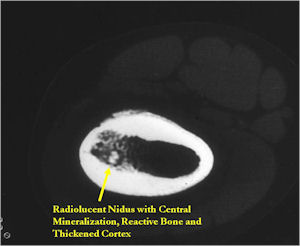

CT Scan:

- Well defined nidus with a smooth peripheral margin; +/- mineralization (CT more sensitive than XR and MRI for detecting mineralization); CT is better for detecting nidus in presence of exuberant sclerosis

- Lucent nidus surrounded by a zone of marked sclerosis

- The nidus may demonstrate mineralization/ossification usually from the center outward that appears as a central zone of density within the nidus

- The periosteal reaction is continuous and often appears as cortical thickening (benign appearing reaction)